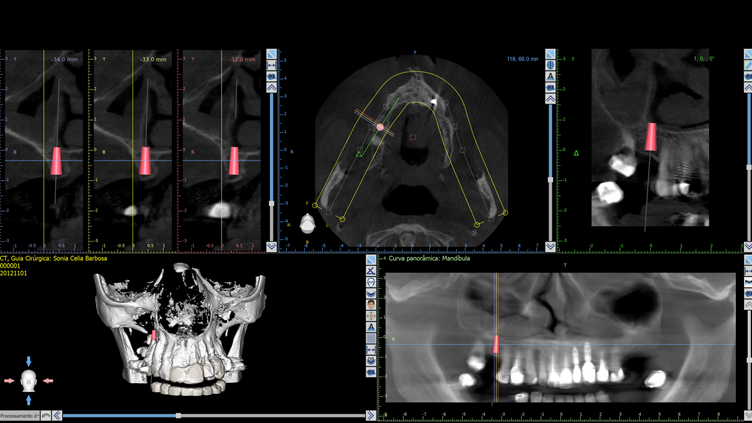

A paciente, de 57 anos, apresentava ausência do dente 16 e queixa mastigatória. A qualidade óssea foi estimada como tipo III (osso trabecular moderadamente denso) e, diante do biotipo periodontal favorável (gengiva espessa), optou-se pelo implante Cone Morse Maestro Superiore 4,0 × 0,9 mm. Sua macrogeometria favorece a formação óssea inicial e otimiza a estabilidade mesmo em osso de densidade moderada, permitindo alto torque de inserção sem compactação excessiva graças às câmaras de cicatrização que aliviam a pressão interna.

No planejamento protético, definiu-se o uso de um pilar Ideale 4,5 × 4 mm, rotacionalmente livre, que permite instalação em qualquer posição e pode receber coroas cimentadas ou parafusadas. A escolha visava otimizar a resposta tecidual e oferecer flexibilidade restauradora. Optou-se por coroa unitária parafusada diretamente ao pilar, confeccionada em zircônia monolítica pela sua durabilidade e estética. O fluxo seria totalmente digital: após a osseointegração, o pilar seria escaneado com scan body específico e a coroa desenhada virtualmente para fresagem em zircônia de alta resistência.